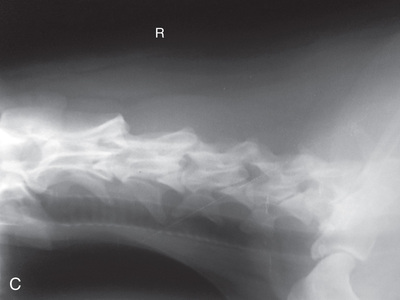

High-quality images are needed to see subtle changes in bone opacity, shape, and angulation of the vertebrae or vertebral column1,2 (Table 20.1). The common views of this portion of the axial skeleton are the lateral (L) and ventrodorsal (VD) views of the cervical, thoracic, thoracolumbar, lumbar, lumbosacral, sacral, and caudal vertebrae. Depending on the size of the patient, a full survey study is either four or five images of each orthogonal view.

Cat survey studies of the vertebrae are often part of the whole-body view. For both the dog and the cat, coned-down views are important for areas of interest. Dynamic views of the vertebrae are not common in cats but can be completed.